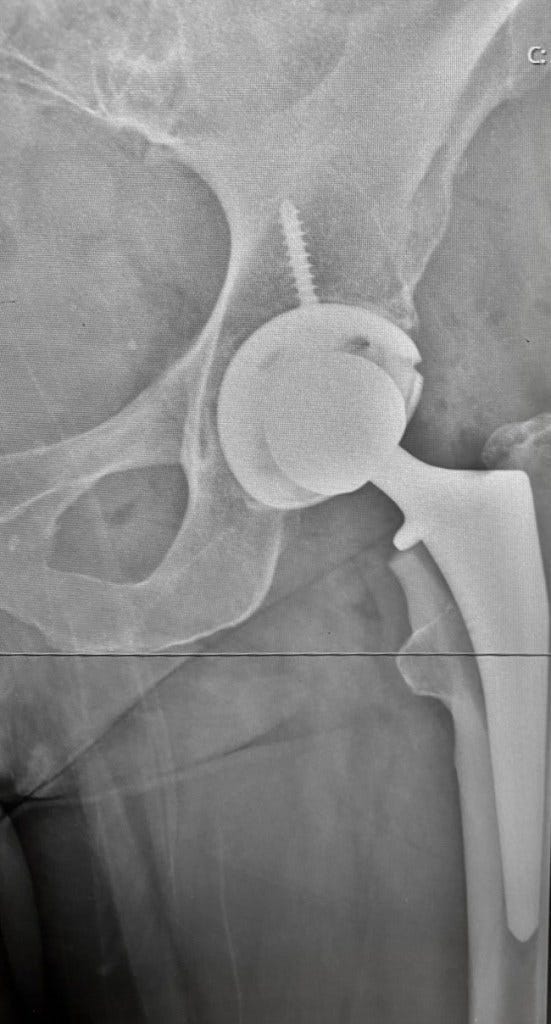

It started with relentless knee pain that would not go away and it was time to see a doctor. Mr. Mazin Ibrahim took one look at my walking and, with experienced confidence, says. “It’s not your knee. It’s your hip, it’s completely worn away and here are the X-rays to prove it.”